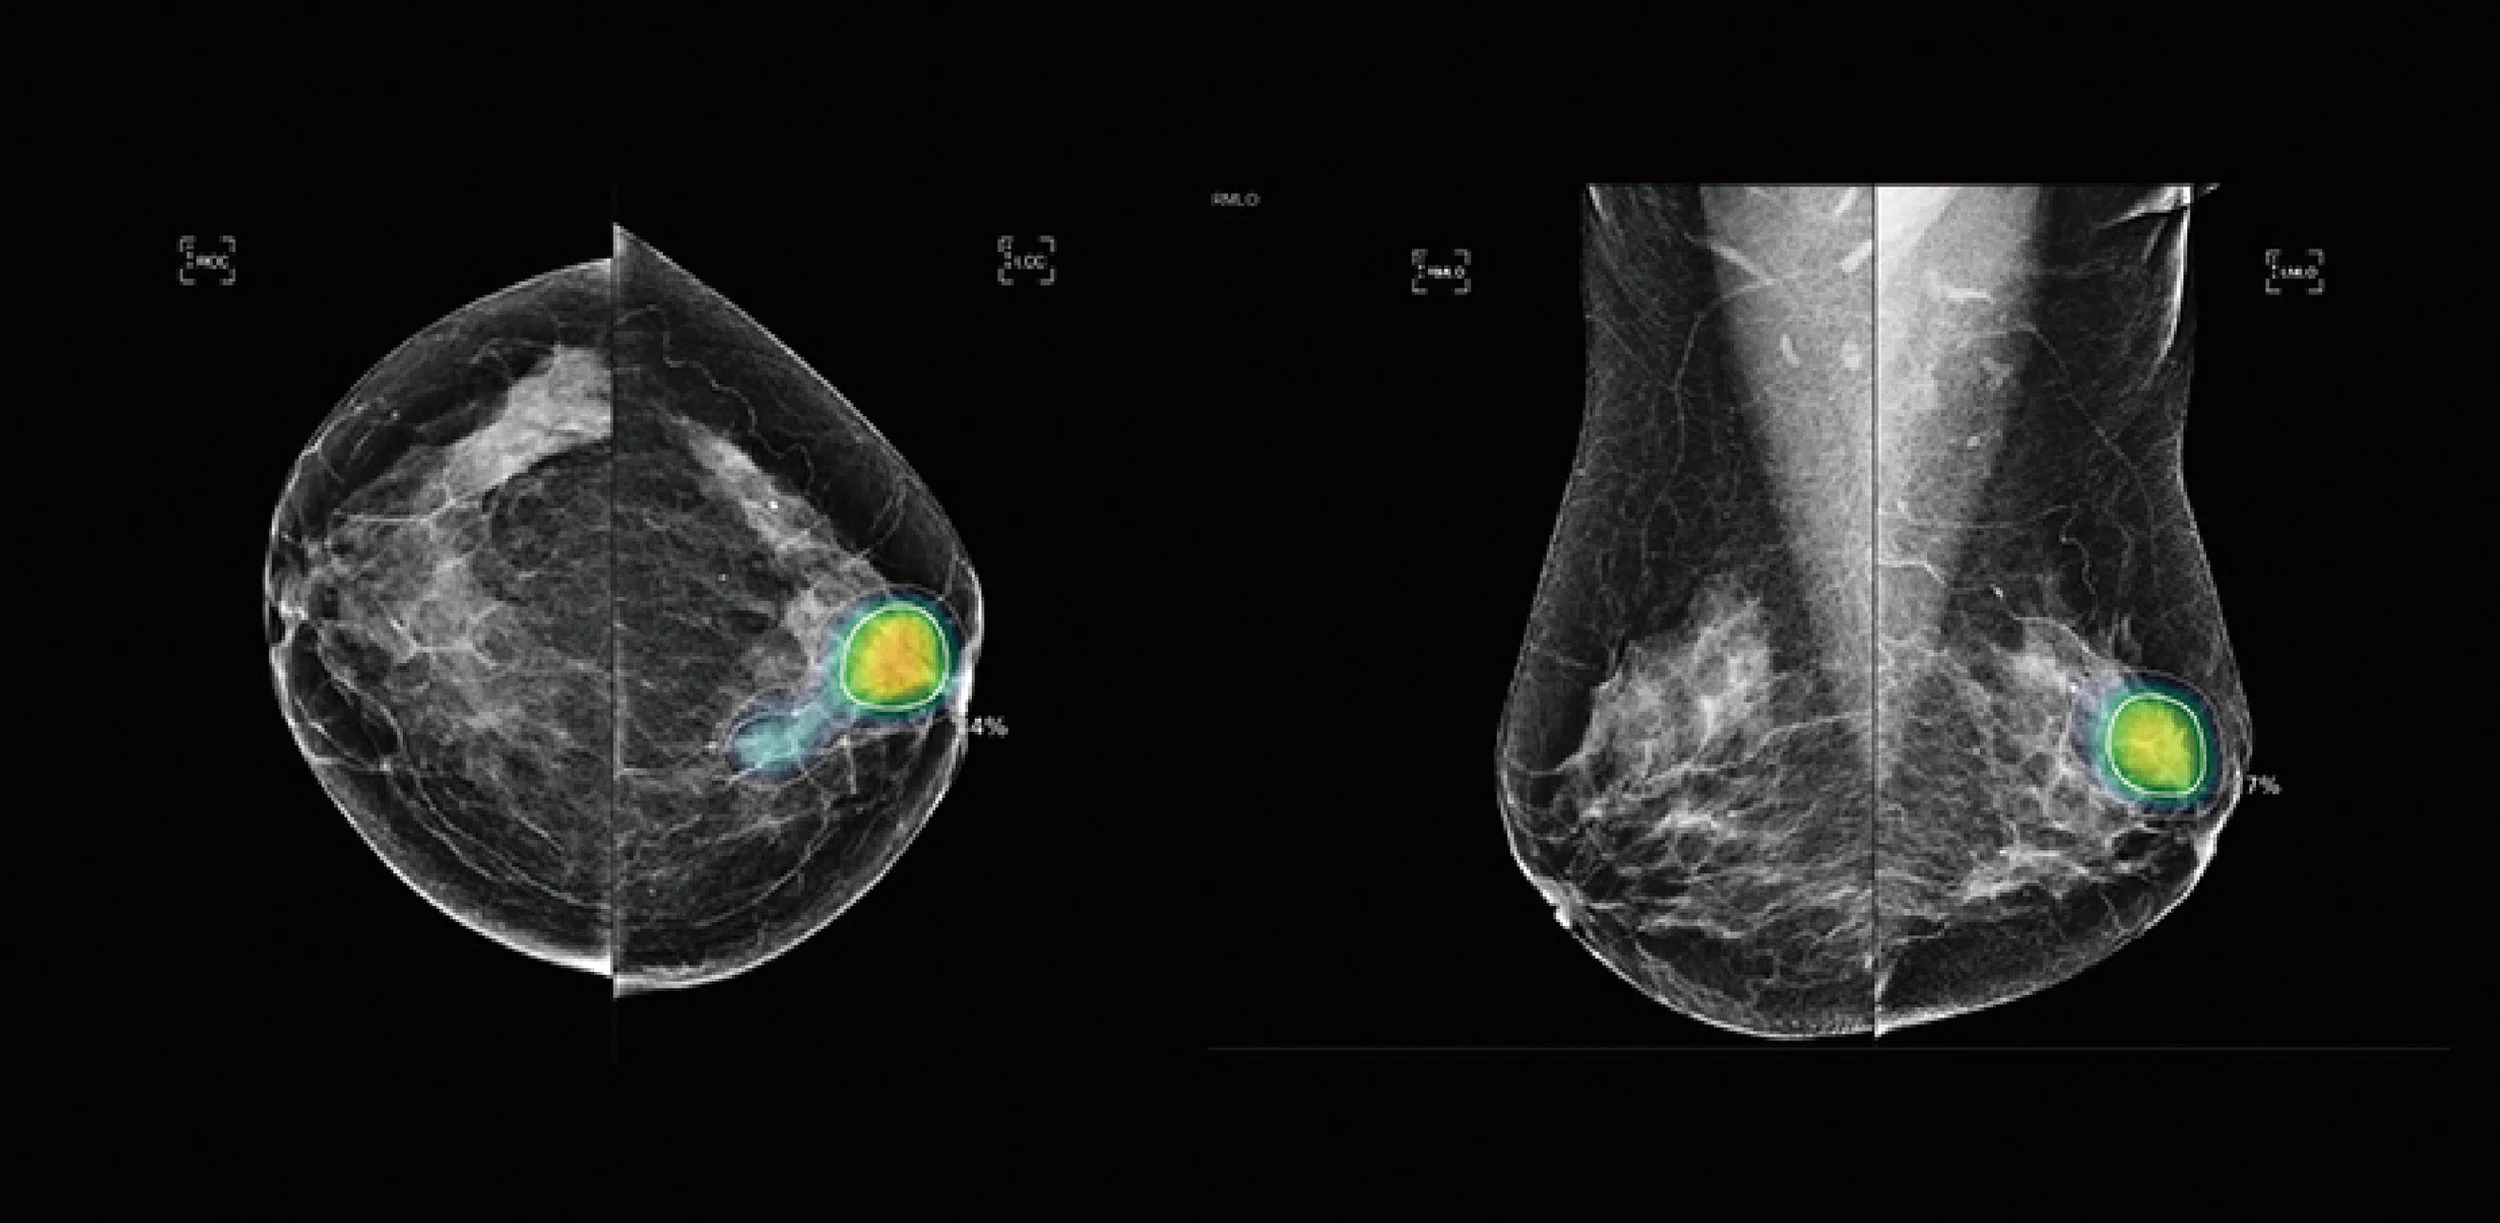

Figure 1: Radiologist review: no cancer detected.

Abnormality Score: 84

Figure 2: SecondReadAI™ review: suspicion of breast cancer detected (indicated by yellow highlighted area).